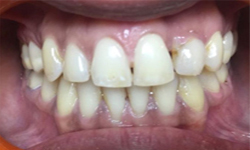

(7) Clinical Case-Veneer

Before Treatment

After Treatment

This female patient, with age 28 yrs came with a complaint of dirty teeth and an unaesthetic tooth in upper front left side of mouth. The patient has been treated with a thorough oral prophylaxis followed by veneering of the tooth.